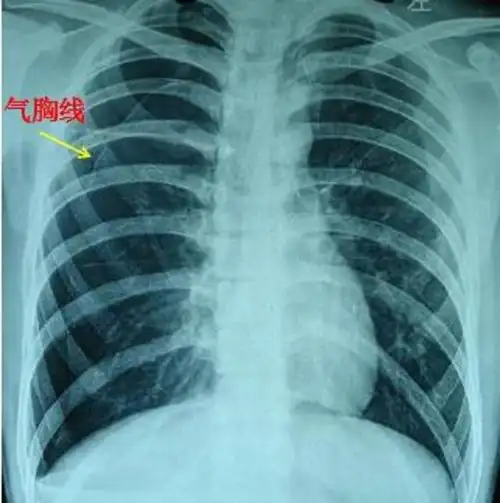

气胸x线胸片图解

拍胸片可见病侧肺明显"压缩"(类似气球漏气瘪掉)及"气胸线",如图:自发